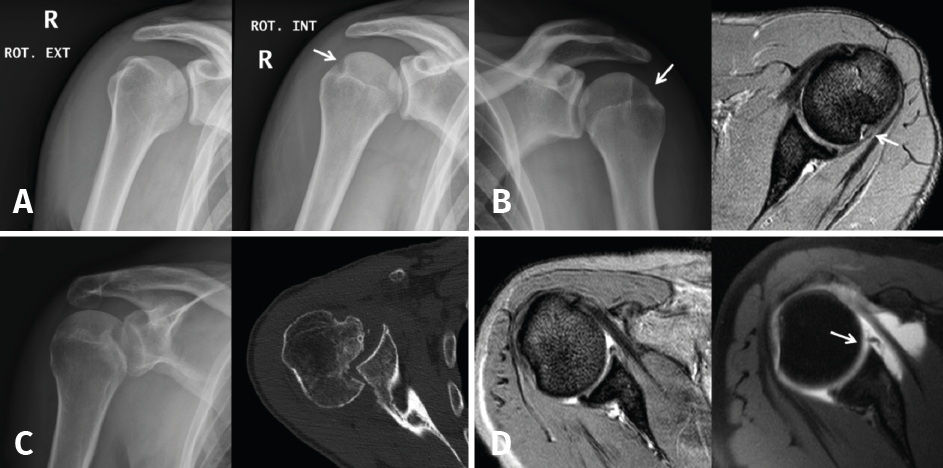

Small Hill-Sachs lesions (HSLs) in AP projection are only visualized with the shoulder in internal rotation (Figure 5A and B), while larger lesions can be seen in both internal rotation and external rotation(20) - the axillary projection affording better visualization of HSLs, however. For assessing glenoid bone loss, it is advisable to use an axillary projection or modified Bernageau projection, with a sensitivity and specificity of over 90%(20,21).

Figure 5. A and B: two cases of patients with Hill-Sachs lesions. A: comparison showing that it is easier to visualize the defect with the shoulder in internal rotation, especially in the case of a small defect; B: the same Hill Sachs lesion is observed on a comparative basis in the plain radiograph and MRI scan; C: computed axial tomography (CAT) view of a reverse Hill-Sachs lesion; D: ALPSA type lesion in conventional magnetic resonance imaging (MRI) and arthro-MRI. The latter technique is useful in the event of diagnostic doubt, since it offers more precise information about the type and characteristics of the capsulolabral lesion.